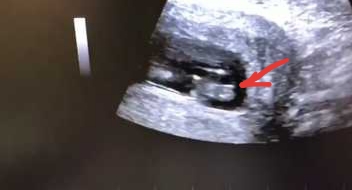

Пол малышаДевочки привет)вот наши гениталии с первого скрининга опытные подскажите?На фото видео половой бугорок вроде вниз смотрит)

Очень маленький масштаб. Думаю это будет пальцем в небо . Подождите недель до 16

Если имеется в виду что вот это бугорок, то мне кажется, он вздернут. Но вообще ракурс и масштаб очень путают)